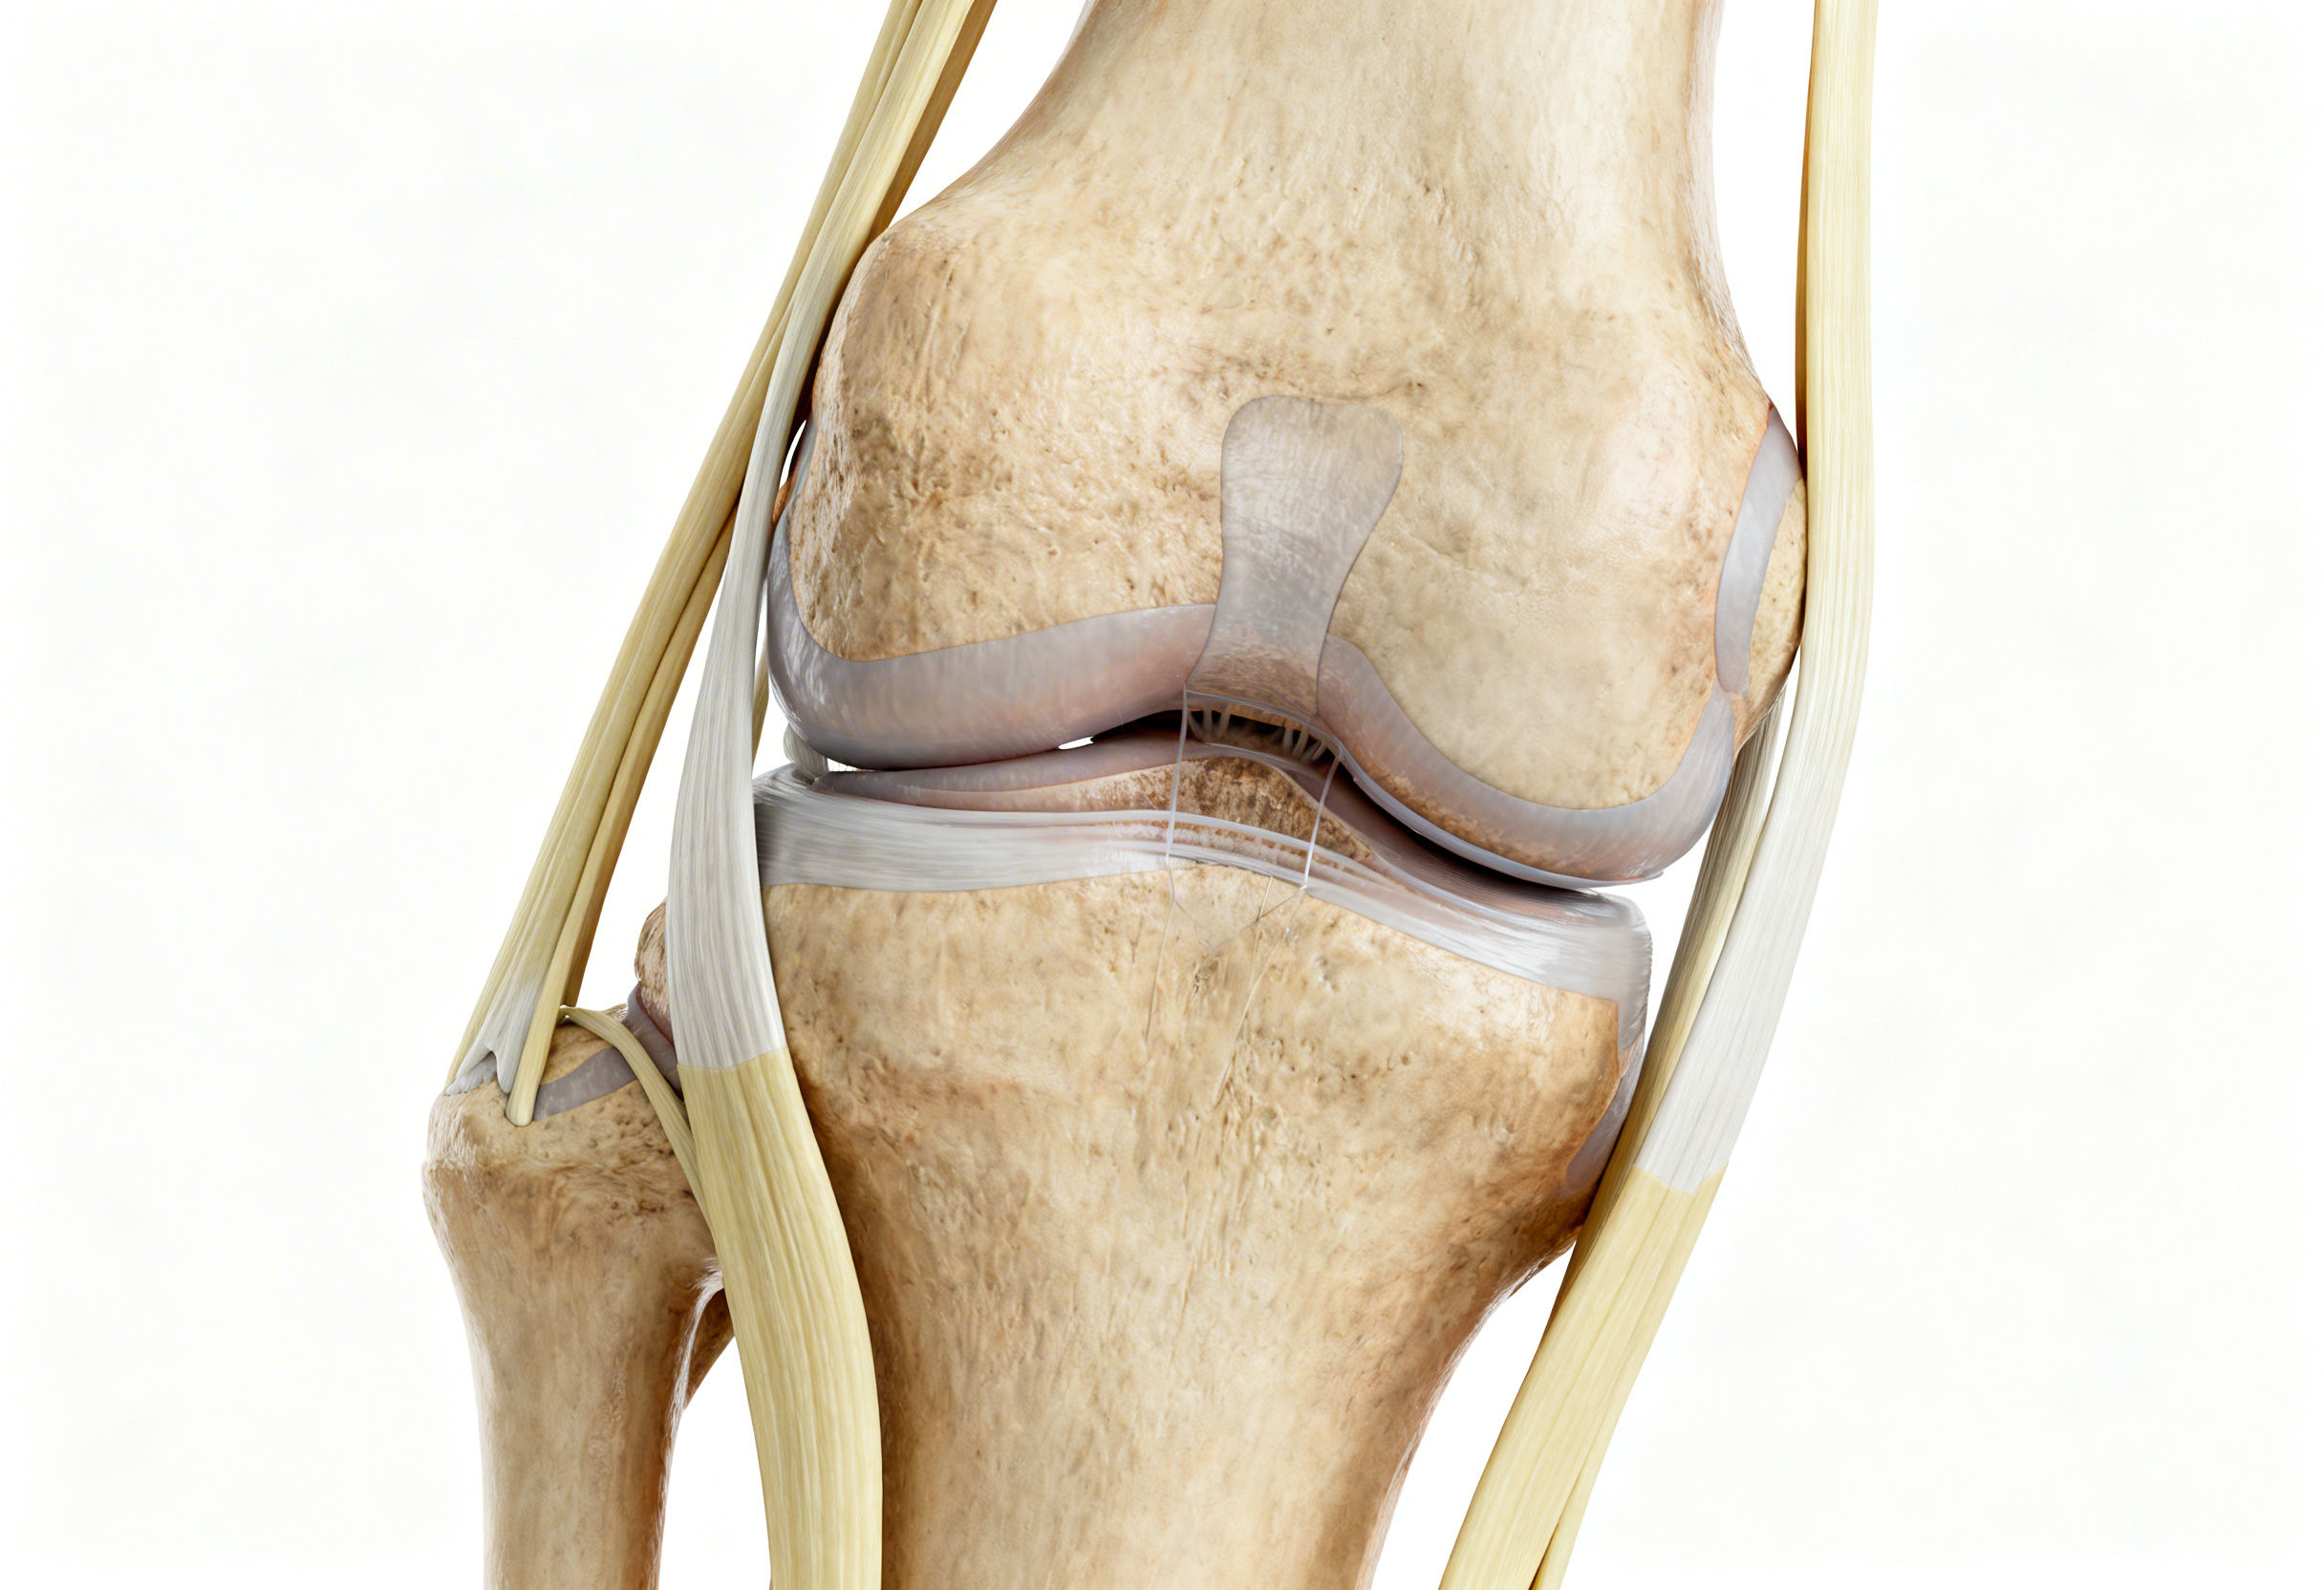

Functional Knee Anatomy and the Role of Ligaments

The knee is not a simple hinge. It is a dynamically stabilized joint that relies on balanced tension from multiple ligamentous structures.

Key stabilizing ligaments include:

• Anterior Cruciate Ligament (ACL)

• Posterior Cruciate Ligament (PCL)

• Medial Collateral Ligament (MCL)

• Lateral Collateral Ligament (LCL)

• Posterior capsule and coronary ligaments supporting the meniscus

These ligaments function together as a tension network. When intact, they keep the femur, tibia, and patella aligned during movement. When one or more ligaments become lax, the joint loses its mechanical precision.

Even a few millimeters of elongation can disrupt normal biomechanics. This instability often does not show clearly on static imaging such as MRI, which is taken without load or movement. Clinical examination frequently reveals instability that imaging misses.